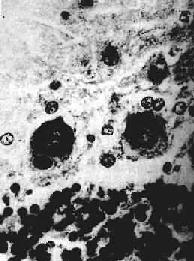

2.组织变化脊膜显示广泛的充血和炎性细胞浸润,以淋巴细胞和浆细胞为主,有时也可见中性粒细胞;脊髓前角充血、水肿明显,运动神经元有不同程度的变性和坏死(中央性Nissl小体溶解,核浓缩、溶解,鬼影细胞出现,大量神经元脱失)伴淋巴细胞、巨噬细胞、中性粒细胞浸润和小胶质细胞增生。病变晚期噬神经细胞现象突出,并有多量泡沫细胞形成和星形胶质细胞增生,形成胶质瘢痕(图16-15)。

图16-15 脊髓灰质炎

脊髓前角内运动神经细胞变性坏死及消失,胶质细胞增生,并有粒细胞浸润

3)软化灶形成灶性神经组织的坏死、液化,形成镂空筛网状软化灶,对本病的诊断具有一定的特征性。病灶呈圆形或卵圆形,边界清楚(图16-16),分布广泛,除大脑(顶叶、额叶、海马回)皮质灰、白质交界处外,丘脑、中脑等处也颇常见。关于软化灶发生的机制至今尚未能肯定,除病毒或免疫反应对神经组织可能造成的损害外,病灶的局灶性分布提示,局部循环障碍(淤滞或小血管中透明血栓形成)可能也是造成软化灶的一个因素。

图16-16 流行性乙型脑炎

脑组织内有多发性镂空软化灶